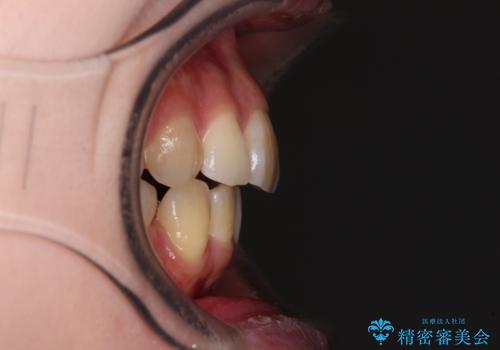

- 奥歯の欠損と、抜歯矯正の後戻りを気にして来院された患者様です。

上下前歯をワイヤー保定していましたが、強い舌の突出癖により上下ともにスペースができ、上下前歯は非接触になっていました。

また、上顎臼歯は虫歯により抜歯されてから放置されている状態でした。

舌のトレーニングをしっかりと行っていただきながらワイヤー装置により矯正治療を行い、途中でインプラントを埋入し、矯正治療後に補綴治療を行うこととしました。